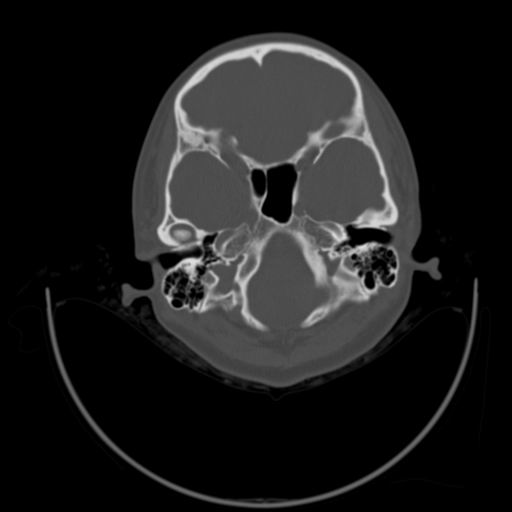

以下是引用随光逐影在2009-3-14 7:58:00的发言:[br]双耳——颞骨ct轴位平扫未见明确异常。